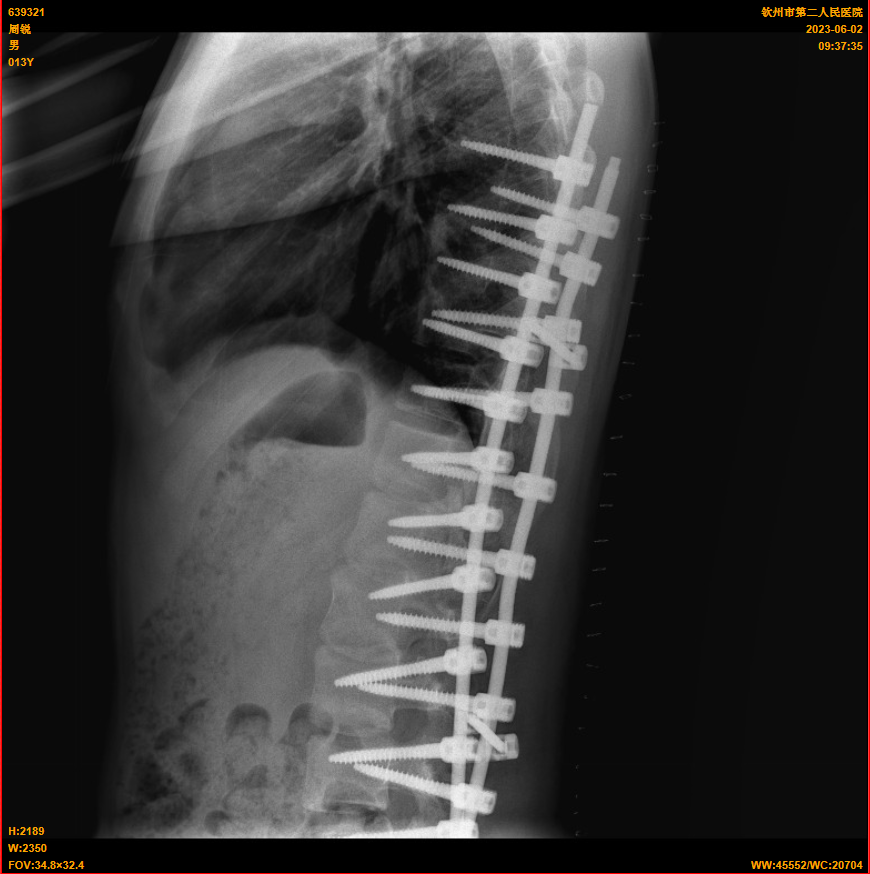

近日,我院脊髓脊柱外科(骨外科三区)成功为一名13岁的青少年小明(化名)成功实施特发性脊柱侧弯矫正手术。术后身高从原来的158cm增高至164cm。该手术的成功施行标志着我院脊髓脊柱外科手术水平又迈上了一个新台阶。

入院骨外科三区(脊髓脊柱外科)后,立即给予完善相关检查,检查结果排除了先天性骨结构异常、脊髓神经等疾病所致脊柱侧弯。结果提示小明患的是:特发性脊柱侧弯!

为了给予小明及时,最优、个性化的治疗,骨外科三区(脊髓脊柱外科)专家团队结合检查结果对小明的病情进行详细的分析和讨论,明确手术方式和手术部位,并与团队提前做好各项术前准备,最终确定为特发性脊柱侧弯矫正手术,手术由仇继任主任医师、罗坤烈副主任医师等专家为小明开展。术中,经过精密计算,成功将小明的脊柱进行了矫正,使其身体恢复了平衡,术后2天,小明已经可以在胸腰椎支具固定下进行下床活动并逐步进行功能锻炼。术后测量,小明的身高也从原来的158cm增高至164cm,患者及其家属对手术效果非常满意。目前,患者恢复良好,已经顺利出院,出院时身体平衡稳定。